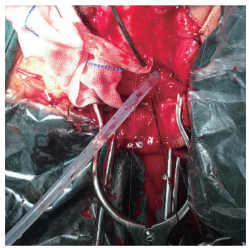

1.3.3 切取口腔黏膜碘伏消毒口腔及黏膜,无菌记号笔标记舌下黏膜、颊黏膜或下唇黏膜取材部位。取舌黏膜时要避开舌下腺导管开口,切取颊黏膜时,要避开腮腺导管开口,舌下黏膜单侧最大可取1.5 cm×7 cm,如 > 15 cm的超长段尿道狭窄,可双侧取材,亦可将两侧舌下及舌尖下部分一并选取。肾上腺素生理盐水黏膜下注射(浓度为1∶200 000~1.100 000),后切取黏膜条,创面5-0可吸收缝线间断或连续关闭。注意在取唇黏膜后压迫止血,勿缝合,确需缝合者,术后1 d即拆除缝线,以防术后唇内翻。使用前需剔除黏膜下脂肪及纤维组织备用,见图 3。

| 图 3 术中取材之口腔黏膜 Fig.3 Intraoperative oral mucosa |